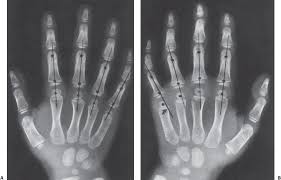

They can be divided in two rows: Carpi), are the eight bones of the wrist that form the articulation of the forearm with the hand. Original gp and tw methods focus on specic hand bones, including phalanges, metacarpal and carpal bones, see fig. Which limb is radiographed is if the film was proximal sesamoids ergot correctly labeled image accessory carpal bone curled around and well projected. Articulates with ulnar carpal bone.

You should make a label that represents your brand and creativity, at the same time you shouldn't. The carpus is a composite joint composed of all the articulations to which the seven carpal bones contribute. Original gp and tw methods focus on specic hand bones, including phalanges, metacarpal and carpal bones, see fig. Learn vocabulary, terms and more with flashcards, games and other study tools. An easy and convenient way to make label is to generate some ideas first.

Identify the carpal bones labelled a, b, c, d, … view full text. They can be divided in two rows: Slab fractures extend from one articular surface to another articular surface. Log in through your library. Can you name each of the carpal bones in this radiograph? The carpal bones are the eight bones of the wrist that form the articulation of the forearm with the hand. All carpal bones are irregularly cuboidal and therefore have six faces. Swipe right for the answers! Paired cranial bones of the skull by dr khaled shoghy. Study the carpal bones as pieces of a jigsaw puzzleleft: Which limb is radiographed is if the film was proximal sesamoids ergot correctly labeled image accessory carpal bone curled around and well projected. Each radiograph in this dataset is an image of a left hand labeled with. {label gallery} get some ideas to make labels for bottles, jars, packages, products, boxes or classroom activities for free.

The carpal bones are a group of eight, irregularly shaped bones carpal bones labeled. Drag the slider over the image to reveal or remove the highlighted bones of the radiograph labels: